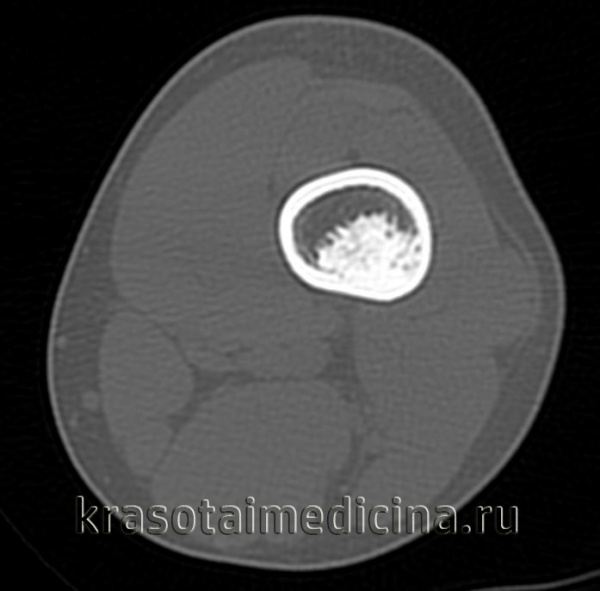

КТ левого бедра. Объемное образование (оссифицированная энхондрома) в нижней трети диафиза бедренной кости.

КТ таза. Метастатическая карцинома подвздошной кости слева с деструкцией костной ткани (красная стрелка) и обширным мягкоктанным компонентом (зеленая стрелка)